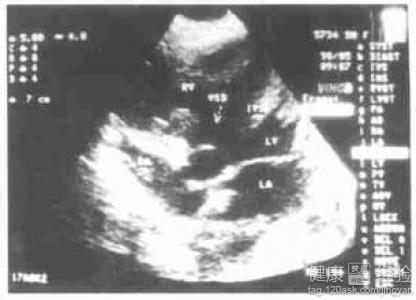

2該病的發生多見於青年的男性人群中,所以一旦發病後,患者可以出現明顯的頭暈或者胸悶的情況,而該病主要病理特點是右室局部或全部心肌為纖維或脂肪組織替代,肌小梁變平,偶有少量單核細胞或炎性細胞浸潤,心內膜可貼近心外膜,病變區心室壁變薄可伴瘤樣擴張,部分病例亦可累及心房和左心室。